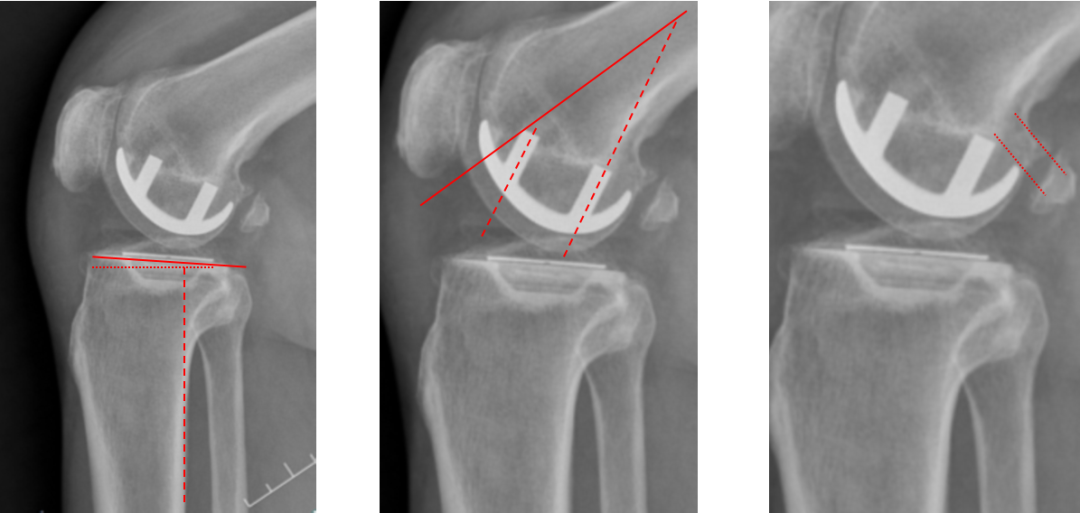

正位片标准胫骨和股骨假体位置

AP位假体位置:胫骨假体外翻3°,内旋10°,外侧缘与胫骨平台外侧缘齐平; 股骨假体长轴与胫骨假体垂直,中线一致。

侧位片标准胫骨和股骨假体位置

侧位片假体位置:胫骨假体后倾5°,与胫骨平台前后缘齐平,股骨假体后倾35°,假体后缘与股骨后髁齐平。

股骨假体偏内放置

AP位胫骨与股骨假体位置:股骨假体无内外内翻,中轴线与胫骨假体中线不一致,偏内侧。

侧位片股骨假体后倾不足

侧位片假体位置:胫骨假体后倾3°,完全覆盖胫骨平台前后缘,股骨假体后倾30°,股骨后髁覆盖不足。

胫骨假体偏厚

胫骨垫片厚度合适:术前外翻畸形矫正至轻度内翻。